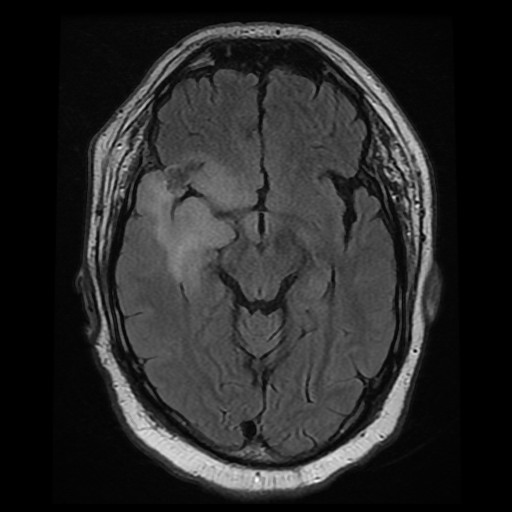

Clinical information: The patient was a 76 year-old man with a history of Parkinson's disease. He developed sudden onset weakness of lower extremities while standing. He did not fall and was able to sit down. There was a brief tremor of his upper extremities but there was no seizure. On furhter work up, an enhancing mass, 2.0 x 1.6 cm, was noted in his right temporal pole. The mass was resected.

Radiology of the Case: The mass is located at the tip of the right temporal lobe causing minimal midline shift. There is heterogensous enhancement suggestive of necrosis (Panel A). There is substantial edema around this mass with extension inot the posterior temporal lobe, insula, and inferior lateral frontal lobe (Panel B). The edematous area on FLAIR probably